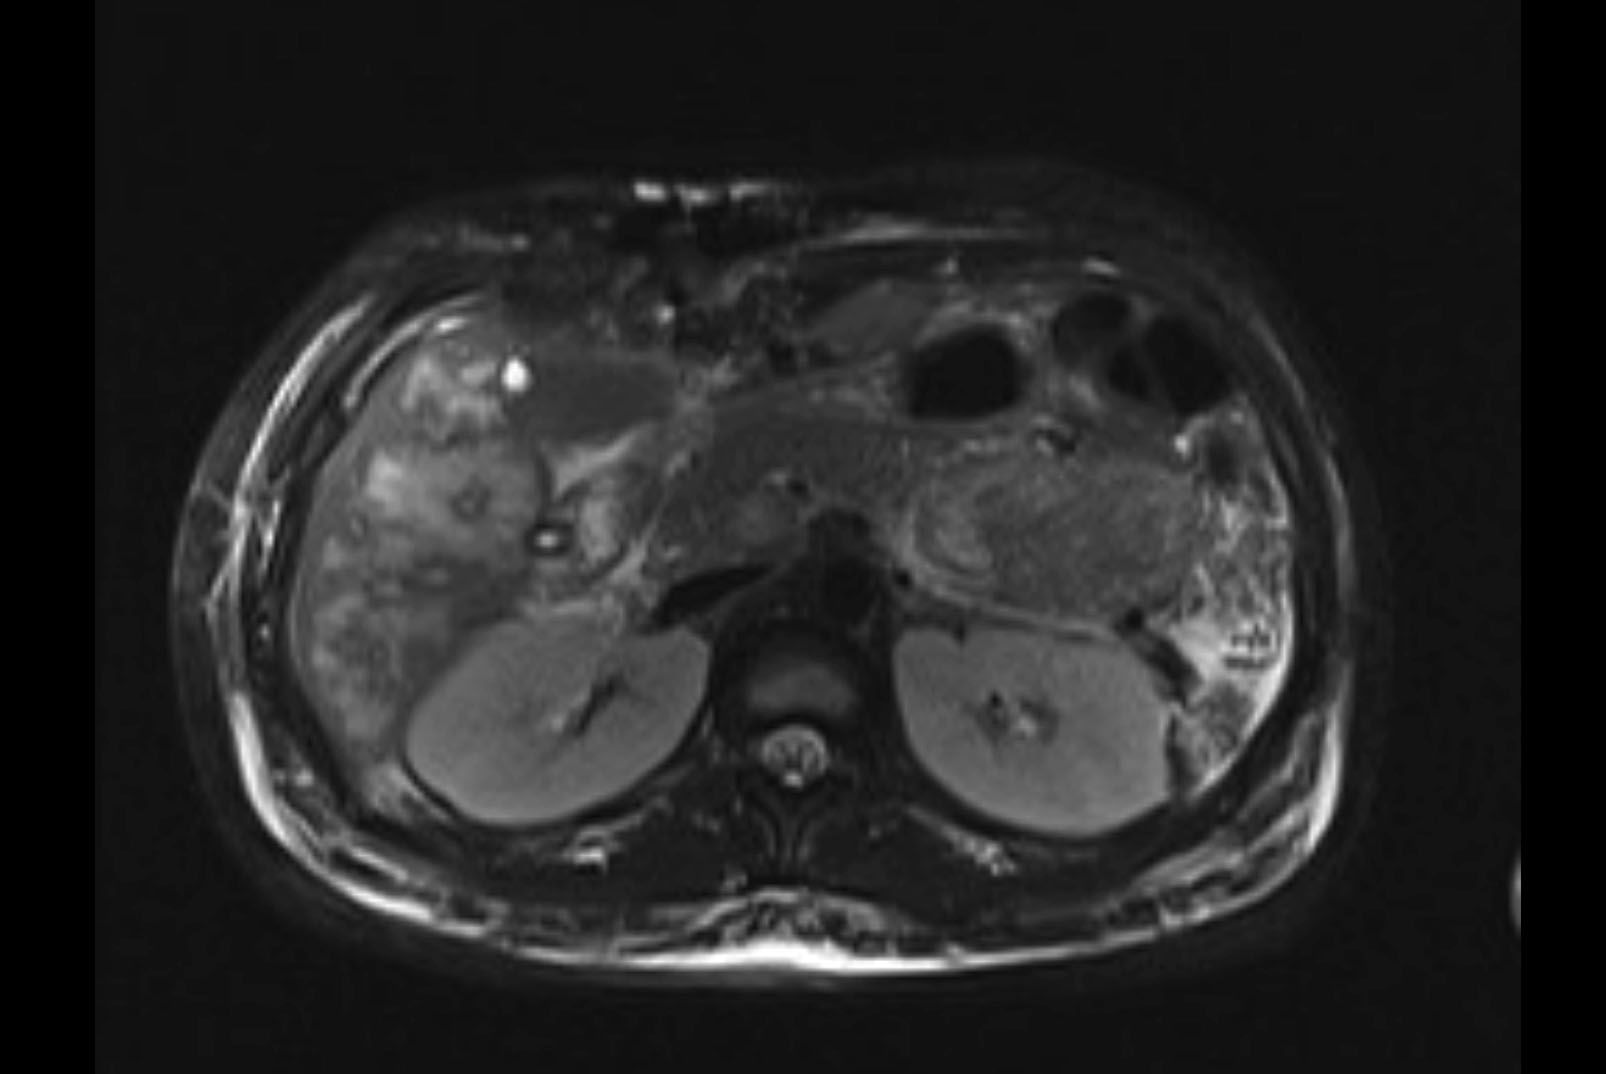

MRI T1

MRI T2